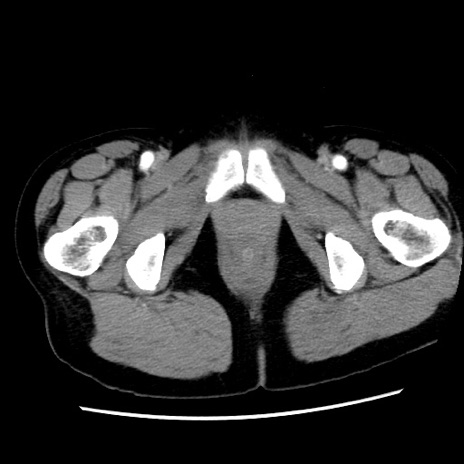

症例10(横断像)

【症例】 50歳代女性

【主訴】 腹痛

【現病歴】前日生レバーを食べた。今朝に排便あり。 昼前に突然発症の腹痛を生じ、当院救急外来を受診した。

【既往歴】 子宮筋腫にてで子宮全摘後

【身体所見】 意識清明、腹部:平坦、軟、下腹部やや左を中心に圧痛・反跳痛あり、筋性防御あり

【データ】WBC 7800、CRP 0.07